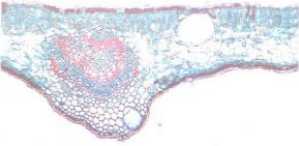

【标题】 九里香 【拼音】 Jiǔ Lǐ Xiānɡ 【英文】 Common Jasminorange, Leaf and Twig, Leaf and twig of Common Jasminorange 【拉丁文】 1.Murraya paniculata (L.)jack.[Chalcas paniculata L.]2.Murraya paniculata (L.)jack.var.exotica(L.)Huang 【异名】 千里香、满山香、五里香、过山香、千只眼、水万年青、千枝叶、千只眼跌打、臭千只眼。 【性味】 味辛;微苦;性温;小毒 【归经】 心;肝;肺经 【功效】 行气活血;散瘀止痛;解毒消肿。主胃脘疼痛;跌扑肿痛;疮痈;蛇虫咬伤 【药用】 为芸香科植物九里香和小叶九里香的茎叶。 【应用】 用于局部麻醉及表面麻醉,以九里香注射液作局部麻醉行大小手术100例,初步观察效果稳定,无不良反应,术中和术后血压、脉搏、呼吸平稳,无肝、肾等损害或其它并发症,无出血、水肿、坏死等现象;镇痛时间长。49例胃次全切除术术后除2例外,均无明显疼痛。缺点是局部刺激较大,腹部手术时腹肌较紧张,对深部手术仍较困难。用量:一个胃次全切除术用12.5%注射液150-200ml(切口浸润),6.25%注射液150-200ml(内脏封闭);小手术则几十ml不等。注射后约10-20分钟即产生麻醉作用,手术时间最长达3小时。小手术均不用术前药,对胃次全切除木术前一般用苯巴比妥钠0.1克或度冷丁50-100mg肌注,对精神较紧张的患者,术时加用冬眠1号半量或全量。用九里香制成表面麻醉剂,涂于咽喉部粘膜表面,作扁桃体挤切术108例,效果良好。涂药后数分钟即出现麻醉作用,痛觉减退。麻醉时间可维持10分钟左右。 【注意】 广西中药志:阴虚火亢者忌用 【用法用量】 内服:煎汤,6-12g;或入散剂;或浸酒。外用:适量,捣敷或煎水洗。 【形态】 1.九里香 常绿灌木或小乔木,高3-8m。树皮苍灰色,分枝甚多,光滑无毛。奇数羽状复叶互生;小叶3-9枚,卵形、倒卵形至近菱形,长2-8cm,宽1-3cm,先端钝或钝渐尖,有时微凹,基部宽楔形或近圆形,全缘,上面深绿色光亮,下面青绿色,密生腺点,腺点干后褐黑色,中脉凸出,均无毛,纸质或厚纸质。3至数花的聚伞花序,顶生或腋生,花轴近于无毛;花大,直径达4cm,极芳香;花柄细长;萼片5,三角形,长约1-2mm,宿存;花瓣5,白色,倒披针形或狭长圆形,长2-2.5cm,有透明腺点;雄蕊8-10,长短相间;子房上位,2室,每室有2胚珠,花往长4-6mm,柱头极增广,常较子房宽。浆果米红色,球形或卵形,长12-20mm,厚5-10mm,先端尖锐;有种子1-2颗,种皮具棉质毛。花期4-6月,果期9-11月。 2.小叶九里香 与九里香不同处:奇数羽状复叶,具小叶3-7,小叶片较小,倒卵形,长2-4.5cm,宽1-2cm,中脉在两面不凸出,革质较厚;花序有花较多,花较小,直径2-3cm,雄蕊及雌蕊均较短小;花药背面有2颗突起的小腺体。子房每室仅1胚珠。果实较小,长8-10mm。花期4-6月,果期7-9月。 【生态环境】 1.生于干旱的旷地或疏林中。 2.生于较干旱的旷地或灌木丛中。 【产地】 1.分布于福建、台湾、湖南、广东、海南、广西、贵州、云南等地。 2.分布于福建、台湾、广东、广西、云南等地。 【栽培】 生物学特性 喜温暖湿润气候,耐旱,不耐寒。最适年平均温度15-18℃,最高月平均温度27-29℃,最低月平均温度1-2℃,能耐极端最低温度-7℃,年降雨量1000-1600mm为宜。以选阳光充足,土层深厚、疏松肥沃的微碱性土壤栽培为宜。 栽培技术 用种子、扦插、压条繁殖,以扦插繁殖为主。种子繁殖:选饱满鲜红成熟果实,去果皮,晾干。春季3-4月或秋季9-10月上旬播种,条播,按行距30cm开沟,种子用细砂混合后播种,覆土1-2cm,浇水,盖草。气温在16-22℃时,经30d左右发芽。待有2片真叶时进行间苗,苗高15-20cm移栽。扦插繁殖:6-7月选1年生健壮枝条,剪成长10-15cm小段,具4-5节,除去下部叶片,仅留顶端2片叶,斜插手苗床,按行株距10cm×10cm扦插,覆土,浇水,保湿。在20℃下约经1个月生根。春季扦插的当年可以移植;秋季扦插的在翌年移植。压条繁殖:雨季选老枝条,割伤后埋入土中,待生根后,与母体分离栽种。 田间管理 生长期间要及时松土除草,适施稀人粪尿1-2次,采叶者以施氮肥为主,采花者增施过磷酸钙。生长后期要注意修剪,剪除过密枝条或徒长枝,以利通风透光。北方冬季室内越冬,最低温度不低于5℃,冬季温度亦不可过高,否则易消耗营养,影响第二年开花。 病虫害防治 病害有九里香枯叶病,可于早春喷70%托布津1500倍液或50%退菌特1000倍液。虫害有蚜虫、红蜘蛛为害嫩枝叶。 【显微特征】 叶横切面:九里香上、下表皮细胞各1列,长方形。叶肉组织不等面型。栅栏细胞2-3列,不通过中脉,内含多数草酸钙簇晶,直径12-20μm。中脉向上微隆起,于下方突出,下表面内侧有4-5列厚角组织。维管束半月形,双韧型,导管呈放射状排列,薄壁细胞排成狭缝状,上方纤维和导管约占1/3:其上下两侧有纤维束,纤维壁厚,木化。油室多数,圆形,直径80-120μm。 【化学成分】 1.九里香叶含多种香豆精类化合物,从广东、云南、海南、台湾等各地产品中已分离得到:九里香甲素(isomexoticin),九里香乙素(murpanidin),九里香丙素(mur-panicin),长叶九里香内酯二醇(murrangatin),长叶九里香醛(murralongin),5,7-二甲氧基-8-(3’-甲基-2'-酮基丁基)香豆精[5,7-dimethoxy-8-(3’-methyl-2’-oxobutyl)-coumarin],海南九里香内酯(hainanmurpanin),7-甲氧基-8-(2’-甲基-2’-甲酰基丙基)-香豆精[7-methoxy-8(2’-methyl-2'-formylpropyl)。Couma-rin],脱水长叶九里香内酯(phebalosin),8-异戊烯基柠檬油素(8-isopentenyllimettin),欧芹酚甲醚(osthole),月橘香豆素(coumurrayin),九里香香豆精(paniculatin),欧前胡内酯(in-peratorin),水合橙皮内酯(meranzin hydrate),九里香酸(paniculin),九里香内酯酮醇(murpaniculol),水合橙皮内酯甲酸酯(coumurrin),水合橙皮内酯异戊酸酯(murrayatin),小芸木呋喃内酯(microminutin),异橙皮内酯(isomeranzin),橙皮油内酯烯酸(auraptenol),长叶九里香内酯二醇乙酸酯(murrangatin acetate),异九里香内酯酮醇异戊酸酯(paniculonolisovalerate),九里香内酯醛(paniculal),异长叶九里香醇烟酸酯(isomurralonginol nicotinate),九里香内酯烯醇醛(panial),顺式欧芹烯酮酚甲醚(cis-osthenon)等。还含黄酮类化合物:3’,4 ’,5,5’,7-五甲氧基黄酮(3’,4’,5,5’,7-pentamethoxyflavone),3,3’,4’,5,5’,6,7-七甲氧基黄酮(3,3’,4’,5,5’,6,7-heptamethoxy flavone),3,3’,4’,5,5’,7,8-七甲氧基黄酮(3,3’,4’,5,5’,7,8-heptamethoxy flavone),3’,4’,5,5’,7,8-六甲氧基黄酮(3’,4’,5,5’,7,8-hexamethoxy flavone),月橘素(exoticin),4’-羟基-3,3’,5,5’,6, 7-六甲氧基黄酮(4’-hydroxy-3,3’,5,5’,6,7-hexamethoxy flavone)等。又含半胱氨酸(cysteine),丙氨酸(alanine),脯氨酸(proline),酪氨酸(tyrosine),亮氨酸(leucine)等游离氨基酸,以及催吐萝芙木醇(vomifoliol),二十八醇(octacosanol),三十一烷(hentriacotane),葡萄糖(glucose)。另含挥发油,油中有:左旋荜澄茄烯(cadinene),邻氨基苯甲酸甲酯(methyl anthranilate),甜没药烯(bisabolene),β-丁香烯(β-caryophyllene),牻牛儿醇(geraniol),3-蒈烯(3-carene),丁香油酚(eugenol),香茅醇(citronellol),水杨酸甲酯(methyl salicylate),硫-愈创(S-guaiazulene)等。 2.小叶九里香叶含香豆精类化合物:过氧橙皮油内酯烯醇(peroxyauraptenol),顺式和反式的去氢欧芹酚甲醚(dehydro-osthole),尤里香醇(murraol),长叶九里香内酯醇酮(murranganon),异长叶九里香内酯醇酮干里光酸酯(isomurranganonsenecioate),长叶九里香内酯二酸乙酸酯(murrangatin acetate),异长叶九里香醇乙酸酯(isomurralonginol acetate),氯化小叶九里香内酯醇(chloticol),7-甲氧基-8-(l’-乙酸氧基-2’-酮基-3'-甲基丁基)香见精[7-methoxy-8(1'-acetoxy-2'-oxo-3'-methylbutyl)coumarin]即是海南九里香内酯,长叶九里香内酯二醇,脱水长叶九里香内酯,小芸木香豆精(minumicrolin),欧芹酚甲醚,橙皮内酯(meranzin),水合橙皮内酯,水合橙皮内酯异戊酸酯,异味决明内酯醇(casegravol),异橙皮内酯,欧芹烯酮酚甲醚,长叶九里香醇,7-甲氧基-8-甲酸基香豆精(7-methoxy-8-formylcou-marin)即是九里香内酯醛,伞形花内酯(umbelliferone),东莨菪素,西伯利亚邪蒿内酯酸(sibiricol),橙皮油内酯烯醇,橙皮油内酯(aurapten),小叶九里香内酯(murraxocin),过氧九里香醇(peroxymurraol),九里香酮(murrayone),右旋赤式长叶九里香内酯二醇(erythro-murrangatin),长叶九里香醛,7-甲氧基-8-(2'-羟基-3’-乙氧基-3'-甲基丁基)香豆精[7-methoxy-8-(2'-hydroxy-3’-ethoxy-3’-methylbutyl)coumarin],7-甲氧基-8-(2’-乙氧基-3'-羟基-3'-甲基丁基)香豆精[7-methoxy-8-(2’-ethoxy-3'-hydroxy-3'-methylbutyl)coumarin]等。还含黄酮类化合物:3,5,6,7,8,3’,4’,5’-八甲氧基黄酮(3,5,6,7,8,3’,4',5'-octamethoxy flavone)即是月橘素(exoticin),3,5,6,7,3’,4’,5’-七甲氧基黄酮,3,5,7,8,3',4',5'-七甲氧基黄酮,5,6,7,3',4',5'-六甲氧基黄酮(5,6,7,3',4',5'-hexamethoxy flavone),3,5,7,3’,4', 5’-六甲氧基黄酮(3,5,7,3’,4',5’-hexamethoxyflavone),5,6,7,3’,4’-五申氧基黄酮(5,6,7,3’,4’-pentameythoxyflavone),3,5,6,8,3',4',5'-七甲氧基黄酮(3,5,6,8,3’,4’,5'-heptamethoxy flavone)等。又含生物碱:九里香碱(murrayanine),O-甲基柯氏九里香酚碱(koenimbine),柯氏九里香碱(koenigine),O-甲基柯氏九里香碱(koenigicine),柯氏九里香酚碱(koenine),吉九里香碱(girinimbine),马汉九里香宾碱(ma-hanimbine)、环马汉九里香碱(cyclomahanimbine),双环马汉九里香碱(bicyclomahanimbine),异马汉九里香碱(isomahanimbine),马汉九里香星碱(mahanimbicine),双环马汉九里香星碱(bicyclomahanimbicine),马汉九里香宁碱(mahanimbinine),柯氏九里香卡任碱(murrayacarine),柯氏九里香洛林碱(koeinoline),双-7-羟基吉九里香碱(bis-7-hydroxygirinimbine)A,双-7-甲氧基吉九里香碱(bis-7-methoxygirinimbine)A,小叶九里香咔唑林碱(exozoline)。另含二萜及三萜化合物:柯伦氏泪柏酮(colensanone),柯伦氏泪柏烯酮(colensenone),羽扇豆醇(lu-Peol),3-表-环鸦片甾烯醇(3-epi-cyclolaudenol)。又含顺式-橙花叔醇(cus-nerolidol),小叶九里香酸(murraxonin)。茎皮含香豆精类化合物:3-(1,1-二甲烯丙基)-花椒内酯[3-(1,1-dimethylallyl)xanthyletin],小叶九里香双内酯(mexolide),近月橘素(mexoticin)。又含生物碱:O-甲基柯氏九里香酚碱,吉九里香碱。还含谷甾醇-β-D-阗乳糖甙(sitosterol-β-D-galactoside)。 另据报道,小叶九里香还含九里香咔唑碱(murrayazoline),橙黄胡椒酸胺乙酸酯(aurantiamide acetate),7-甲氧基-8-(1’-甲氧基-2’-羟基-3'-甲基-△3-丁烯基)香豆精[7-methyoxy-8-(1'-methoxy-2'-hydroxy-3'-methyl-△3-butenyl)couma-rin],7-甲氧基-8-(2'-甲氧基-3'-羟基-3'-甲基丁基)香豆精[7-methoxy-8-(2'methoxy-3'-hydroxy-3'-methylbutyl)coumarin],7-甲氧基-8-(2',3'-二羟基-3'-甲基丁基)香豆精[7-methoxy-8-(2',3'-dihydroxy-3'-methylbutyl)coumarin]。 【理化鉴别】 薄层色谱:取本品粉末2g,加甲醇20ml,回流15min,趁热滤过,浓缩液作供试液;另以新九里香素、橙皮内酯水合物、九里香乙素及九里香丙素作对照品。分别点祥于同一硅胶G-0.7%CMC薄层板上,用氯仿-乙酸-水(4:1:1)展开后,量紫外光灯(254-365nm)下检视。供试液色谱在与对照品色谱相应的位置上,显相同的蓝色斑点。 【药理作用】 1.茎叶煎剂有局部麻醉作用,12.5%浓度用于浸润麻醉,效果尚好,唯局部刺激性较大。对麻醉犬的血压、呼吸无显着影响。 2.从本品石油醚提取物中分得一种不含氮的结晶性成分(分解点91-92℃),对离体鼠肠有明显的松弛作用,能对抗组胺、氯化钡所致的平滑肌痉挛,但对乙酰胆碱引起的平滑肌痉挛无对抗作用。 3.九里香中分得一种糖蛋白,给孕期12-16日的孕兔腹腔注射10mg/kg或羊膜腔注射3mg/胚胎,可使孕兔终止妊娠。 4.同属植物麻绞叶(M.Koenigii)对人的致病性真菌,有特异的抑制作用。 【采收加工】 生长旺盛期结合摘心、整形修剪采叶,成林植株每年采收枝叶1-2次,晒干。 【炮制】 本品洗净、阴干、切段备用,也可捣碎浸酒服 【附方】 治湿疹:九里香鲜枝叶,水煎,擦洗患处。(《福建中草药》) 【参考文献】 1.《生草药性备要》:止痛,消肿毒,通窍,能止疮痒,去皮风,杀疥。2.《岭南采药录》:患百子痰打,用叶一撮,捣烂煮粥,和糖服之。3.《广西中药志》:行气止痛,活血散瘀。治跌打肿痛,风湿,气痛。4.《本草纲目》引傅滋《医学集成》治肚痈,以九里香草捣碎浸酒服,疑即本品。 【图片】 九里香 ![]() 千里香 ![]() 药材九里香 ![]() 药材九里香叶横切面 ![]() (责任编辑:Doctor001) |